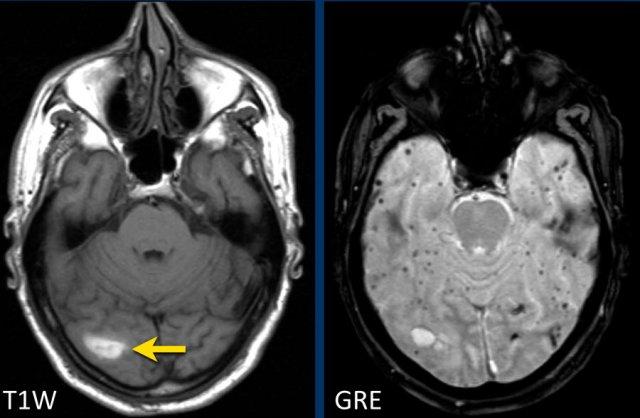

Bệnh nhân này nhập viện với hình ảnh khối máu tụ tiểu não.

Tiếp tục xem hình ảnh chuỗi xung T1W…

Chuỗi xung T1W cho thấy ổ xuất huyết tăng tín hiệu (mũi tên).

Xuất huyết nội sọ do tăng huyết áp cùng với CAA chiếm 80% nguyên nhân gây khối máu tụ trong nhu mô não.

Cần nghĩ đến CAA khi phát hiện nhiều ổ xuất huyết ngoại vi hoặc xuất huyết thùy ở bệnh nhân cao tuổi.